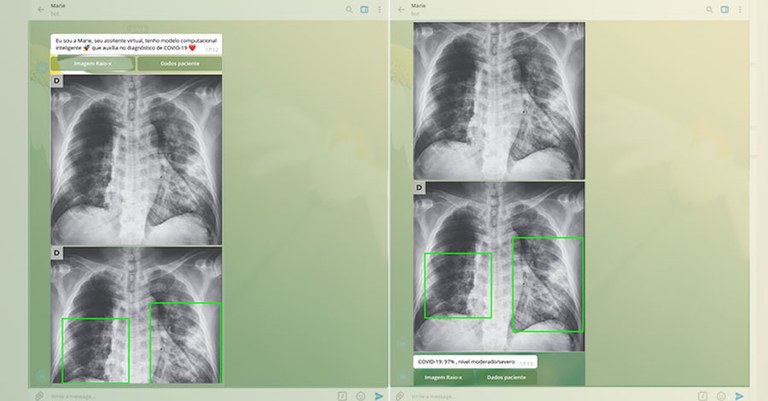

Jornal da USP - Em Ribeirão Preto, um grupo de pesquisadores da Faculdade de Filosofia, Ciências e Letras (FFCLRP) da USP e do Supera Parque de Inovação e Tecnologia de Ribeirão Preto criou um aplicativo capaz de identificar se um paciente está com a covid-19, a partir de uma simples radiografia de pulmão. O aplicativo também pode ser utilizado para fazer triagem de pacientes com suspeita de covid-19, pois permite a análise de várias imagens ao mesmo tempo.

Mesmo com detalhes ainda a serem ajustados, Paula afirma que o aplicativo Marie apresenta uma assertividade de 93% a 98% no diagnóstico de pacientes com a covid-19. “Percebemos que a assertividade cai quando o paciente está na fase inicial da doença, mas em pacientes com grau mais avançado, a assertividade chega a 98%. Então o que precisamos é aprofundar o estudo dos casos leves”.

Outra vantagem do aplicativo Marie, segundo a professora Geraldine Góes Bosco, do Departamento de Computação e Matemática da FFCLRP, que também participou do desenvolvimento, é o fato do médico poder enviar pelo celular várias imagens para triagem e diagnóstico, ou somente uma imagem para diagnóstico. “Isso pode auxiliar o profissional onde quer que ele esteja, pois o aplicativo consegue analisar e processar várias imagens ao mesmo tempo e dar a resposta em poucos minutos.”